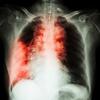

早期肺癌,手术都做完了,还要辅助化疗靶向?

话说有一个名字叫做伊毕七的肺癌患者,他体检的时候发现了一个肺结节,完善了相关检查后考虑恶性的可能大,做了手术,术后病理分期是IB期,他听医生说,这个分期很早,预后很好,他特别庆幸自己有体检的意识,能够早期发现,早期治疗,逢人就说都是体检救了他。